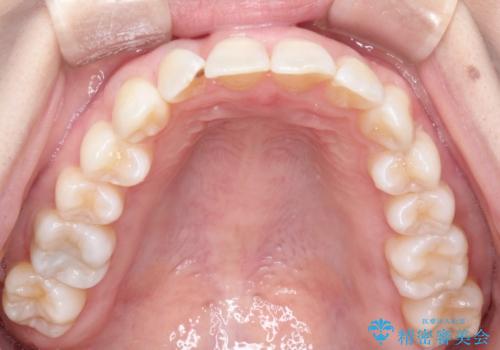

- 上の前歯のねじれを気にされて来院されました。

右上の前から2番目の歯が90度近くねじれて並んでいました。